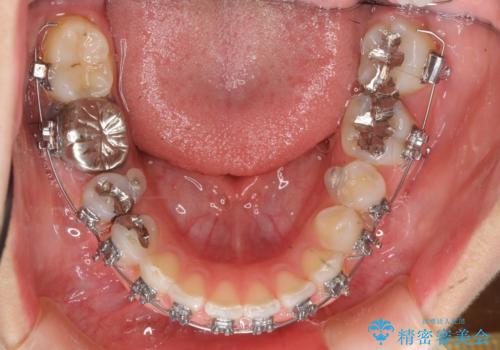

- 矯正装置

- メタル装置

- 3年6ヶ月

- 治療回数

- 10-30回